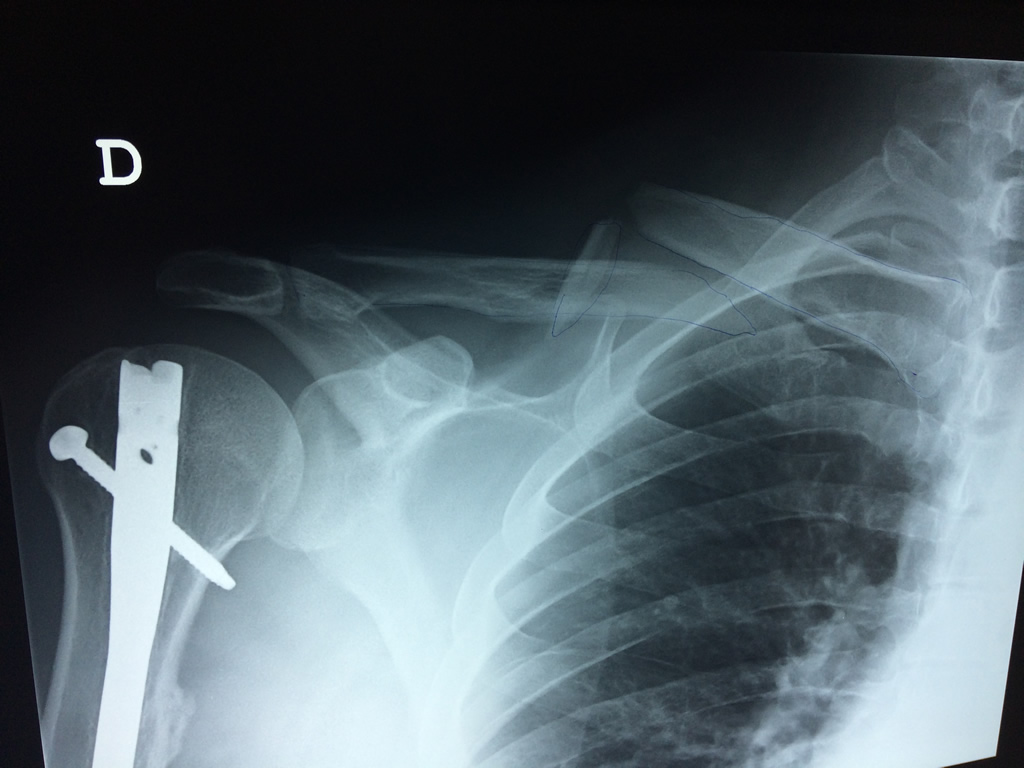

Cirugías de Codo - Clavícula

La clavícula es un hueso largo, con forma de "S" itálica, situado en la parte anterosuperior del tórax. Junto con la escápula forman la cintura escapular. Se puede palpar por toda su longitud y se extiende del esternón al acromion de la escápula, siguiendo una dirección oblicua lateral y posterior.